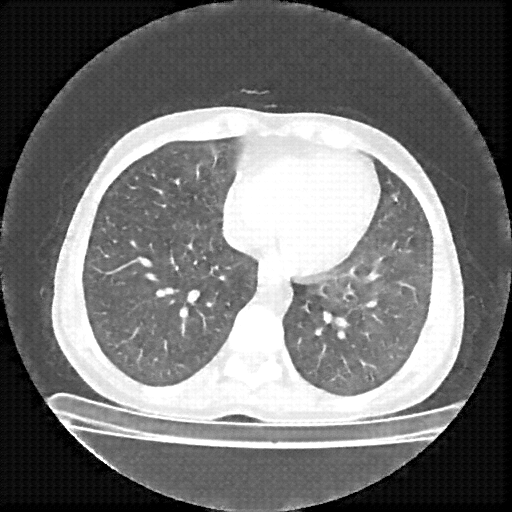

Targeted Slice 70 - Lung Window Analysis (Generated vs Real Venous)

0.527

Lung SSIM

164.1

Lung RMSE

121.4

Lung MAE

Average Lung Window Metrics Across All Slices (112 slices) - Generated vs Real Venous

0.579

Lung SSIM (Avg)

137.7

Lung RMSE (Avg)

95.0

Lung MAE (Avg)

Original VENOUS CT scan

Lung window (WL -600, WW 1500 β†’ Low βˆ’1350, High +150)

Generated VENOUS CT scan (A→B translation)